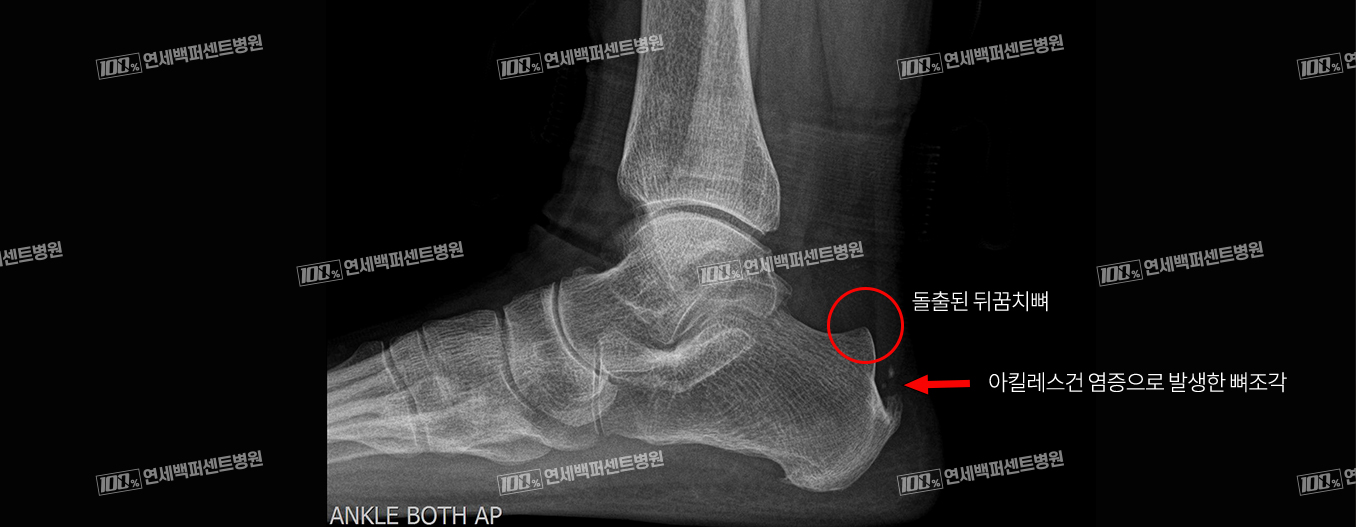

최소침습 해글런드 변형 절제술

긴 절개 없이 최소침습으로 치료!

돌출된 뒤꿈치 뼈와 아킬레스건 염증 동시 치료!

수 차례의 충격파 치료, 주사치료에 반응 없는 난치성 아킬레스건염 해결!

손OO (23.01.09)

손OO (23.03.09)